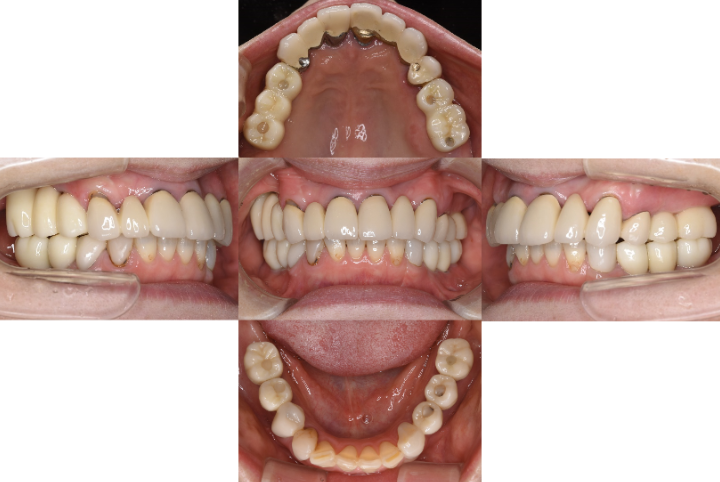

CASE01

初診時

治療終了後5年時

| 主訴 | 入れ歯をやり替えたい |

|---|---|

| 治療内容 | 上下顎とも状態が悪い歯を抜いて奥歯をインプラントで修復しました。 前歯は患者さまの希望のもとそのままにしています。 上顎は骨の高さが足りなかったため、【サイナスリフト】という特殊な手術を行い骨の高さを獲得しています。 術後経過もメインテナンスに通っていただいており、良好な状態を保っています。 |

| 治療期間 | 1年6ヶ月 |

| 治療費用 | 5,060,000円 |

| 費用詳細 | ・サイナスリフト(2か所) 660,000円 ・セデーション(静脈内鎮静法) 110,000円 ・TEC(仮歯) 220,000円 ・インプラント手術+アバットメント+上部構造(9歯) 3,960,000円 ・ポンティック(1歯) 110,000円 |